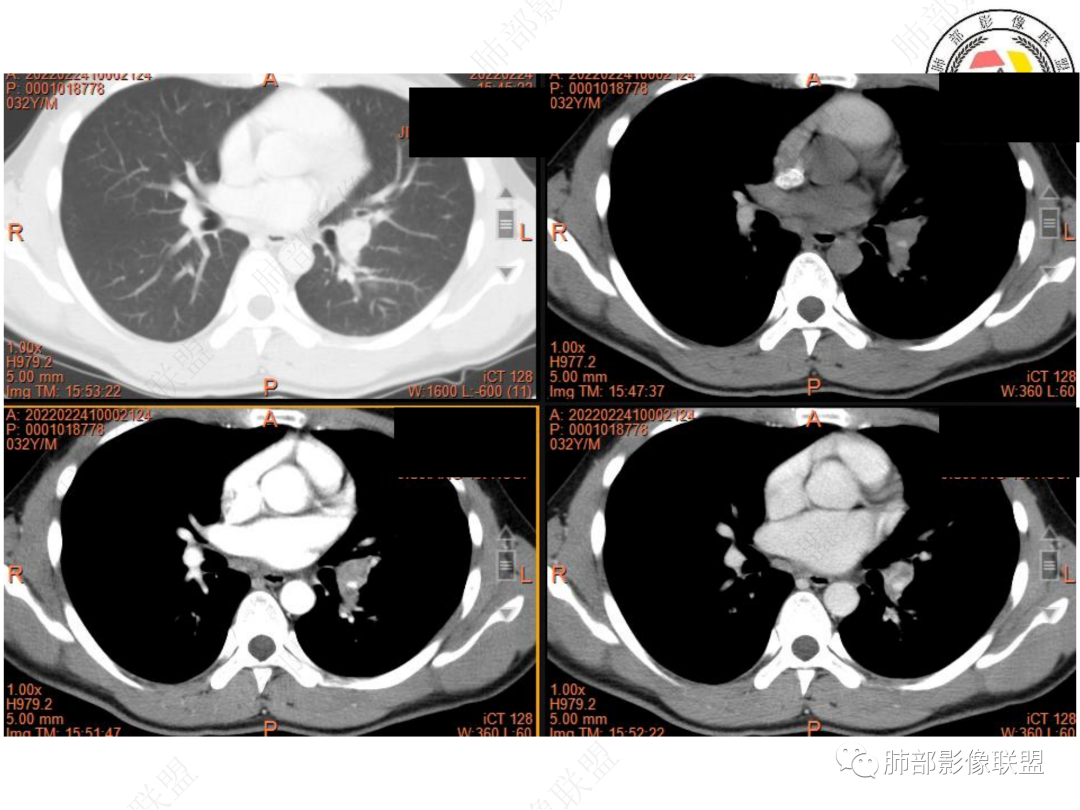

1. 青年男性,偶然发现左肺下叶结节影,左肺门及纵隔内多发淋巴结肿大,并坏死。

3. CT示左肺下叶背段孤立实性密度结节影,边缘比较清楚光滑,总体呈现膨隆感,未见分叶毛刺,少张力,部分层面病灶边缘呈现较清楚磨玻璃样密度影,并于磨玻璃影病灶内可见多发小空泡,未见钙化或空洞,增强后病灶显示不均匀强化,未见低密度液化区。未见卫星病灶。

5. 此病例青年男性,纵隔淋巴结环形强化,易先入为主诊断结核。但左肺下叶背段病灶密度均匀,强化明显,整体具备膨隆感,缺少炎性病灶的平直征,病灶周围未见卫星灶,应想到新生物可能。纵隔及左肺门肿大淋巴结,虽有部分淋巴结环形强化特点,但是部分淋巴结周围血管脂肪间隙小时、密度增高,强化明显。至此,亦可与结核的环形强化区分开来。尽管患者年轻,但恶性征象出现时,仍应当高度警惕。